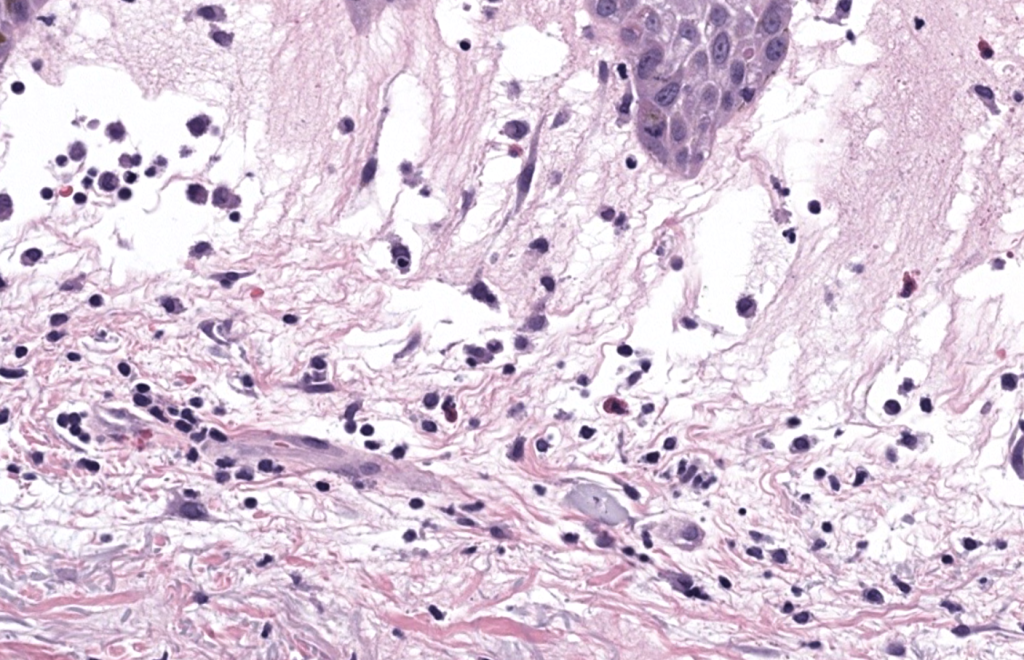

- Definición: dermatosis inflamatoria caracterizada por inicio abrupto de pápulas/nódulos/placas eritemato-violáceas dolorosas, acompañadas con frecuencia de fiebre y marcadores inflamatorios elevados, con infiltrado dérmico neutrofílico (típicamente sin vasculitis primaria). Sweet 1964, Cohen 2007

- Confirmación: biopsia punch. Guhl 2008